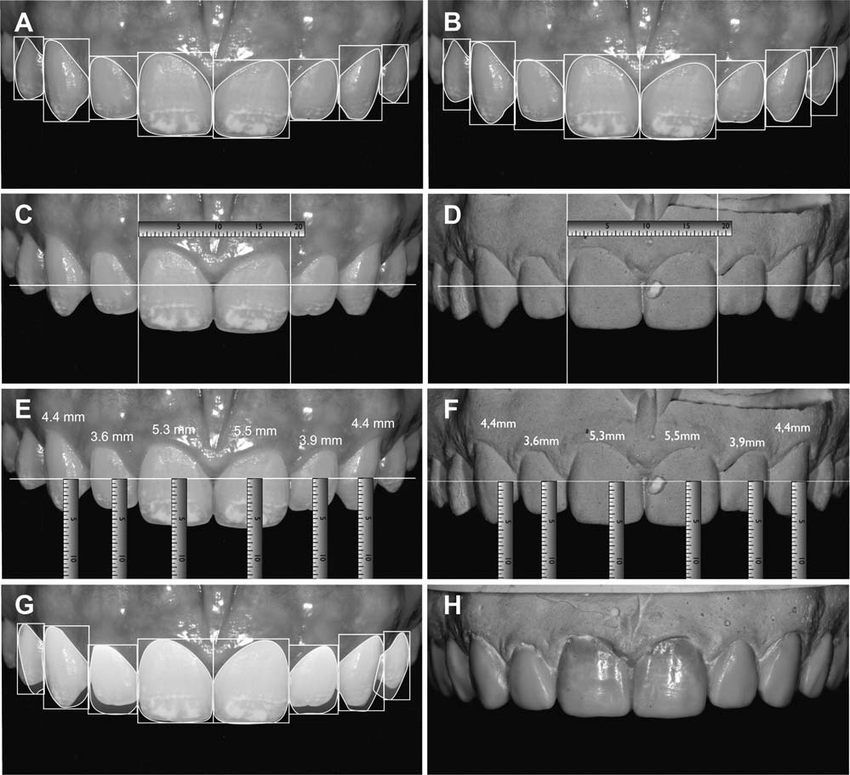

- Esthetics/ Veneers and Smile design